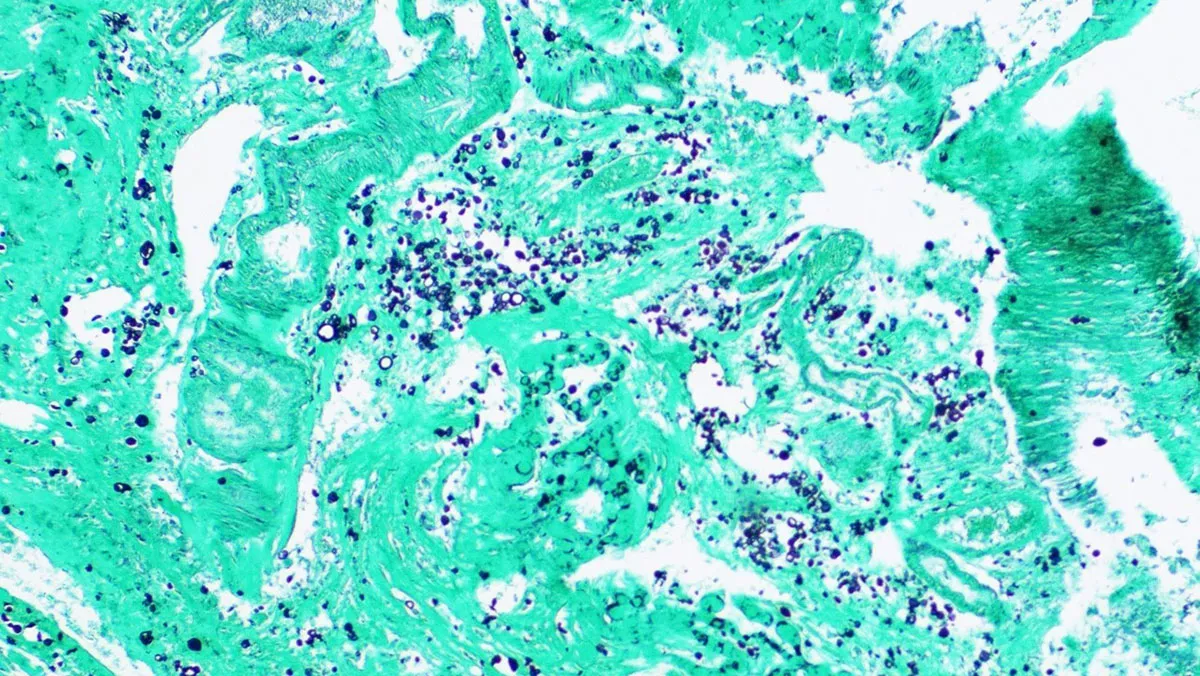

A 47-year-old man with a recent diagnosis of AIDS and diffuse large B-cell lymphoma was hospitalized because of seizures and an enlarging left neck mass. MRI of the brain showed a 2.5 by 1.2 cm lesion in the left inferior parietal lobe, a 1.4 by 0.7 cm ring-enhancing lesion in the right frontal lobe, and other scattered bilateral lesions. A craniotomy was done, and biopsies obtained from the right temple lesion for aerobic, anaerobic, fungal, and mycobacterial cultures, polymerase chain reaction for Toxoplasma, and surgical pathology.

Gram stains, KOH prep, acid-fast stains, and Toxoplasma PCR of the brain tissue were all negative. Representative histopathology slides showing an organism are below.

What is the organism?